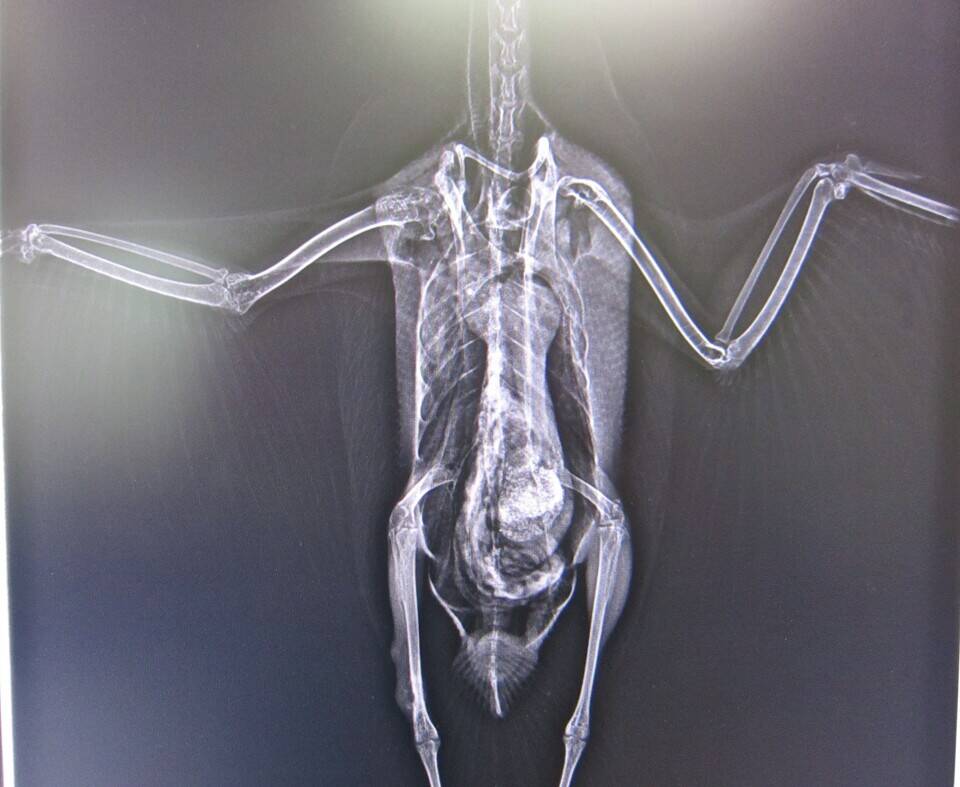

お約束どおり、今回はこの写真からスタート!

ヒント①この鳥はオカヨシガモです。

はい、右肩の脱臼でした。

7月3日のブログ「バードケージメンバー交替(オカヨシガモの巻)」に

登場していたオカヨシガモのレントゲン写真だったのです。

どうです?わかりましたか?

患部をアップにしてよ~く見てみると・・・

左右にズレがあるのがわかりますね。ここが患部です。